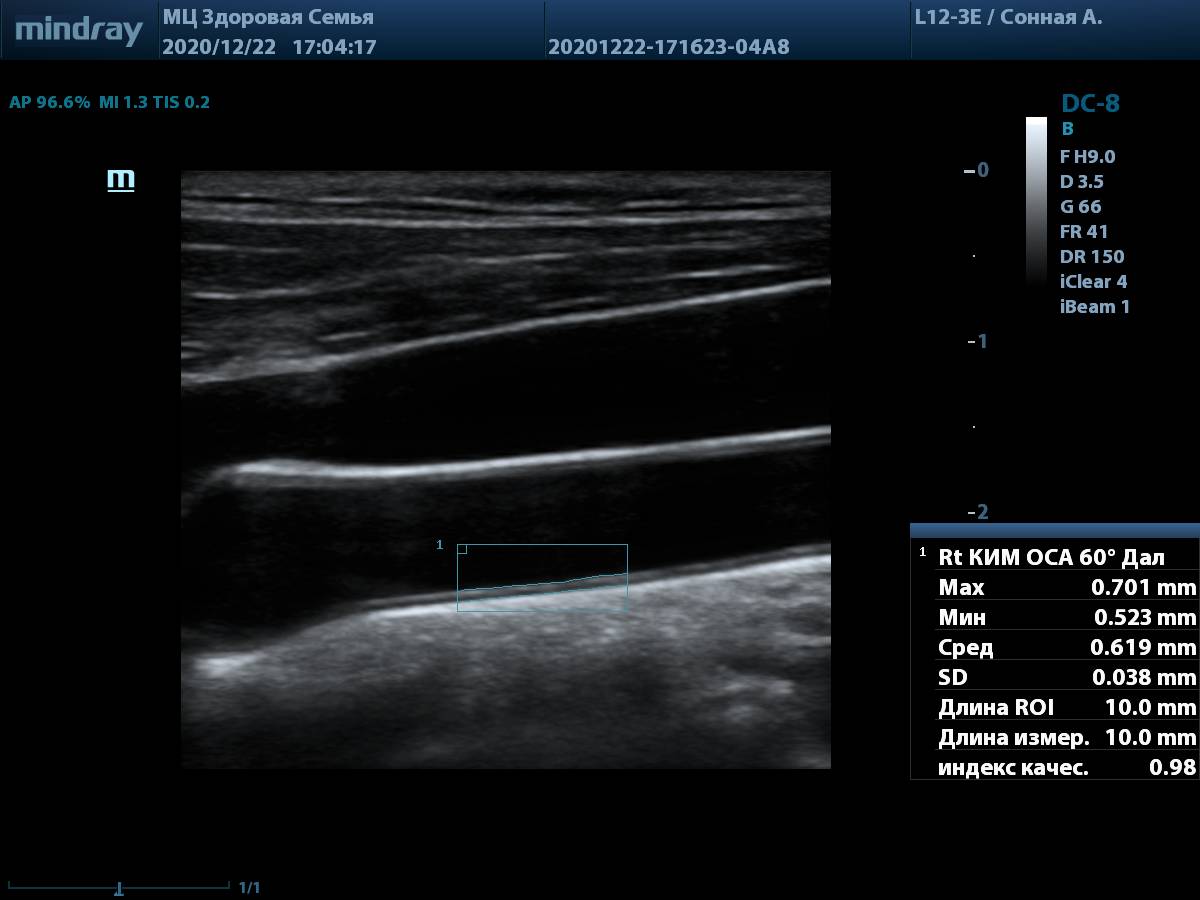

8. Общая сонная артерия (L12-3E) с использованием системы автоматического измерения комплекса интима-медиа, согласно международным стандартам.

Общая сонная артерия, авто IMT